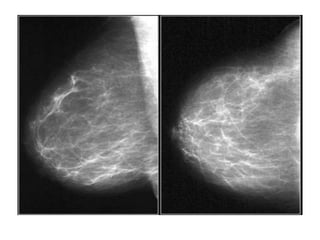

This patient presented with a mass on the mammogram at screening, which was assigned as BI-

RADS 0 (needs additional imaging evaluation).

Additional ultrasound demonstrated that the mass was caused by an intramammary lymph node.

The final assessment is BI-RADS 2 (benign finding).